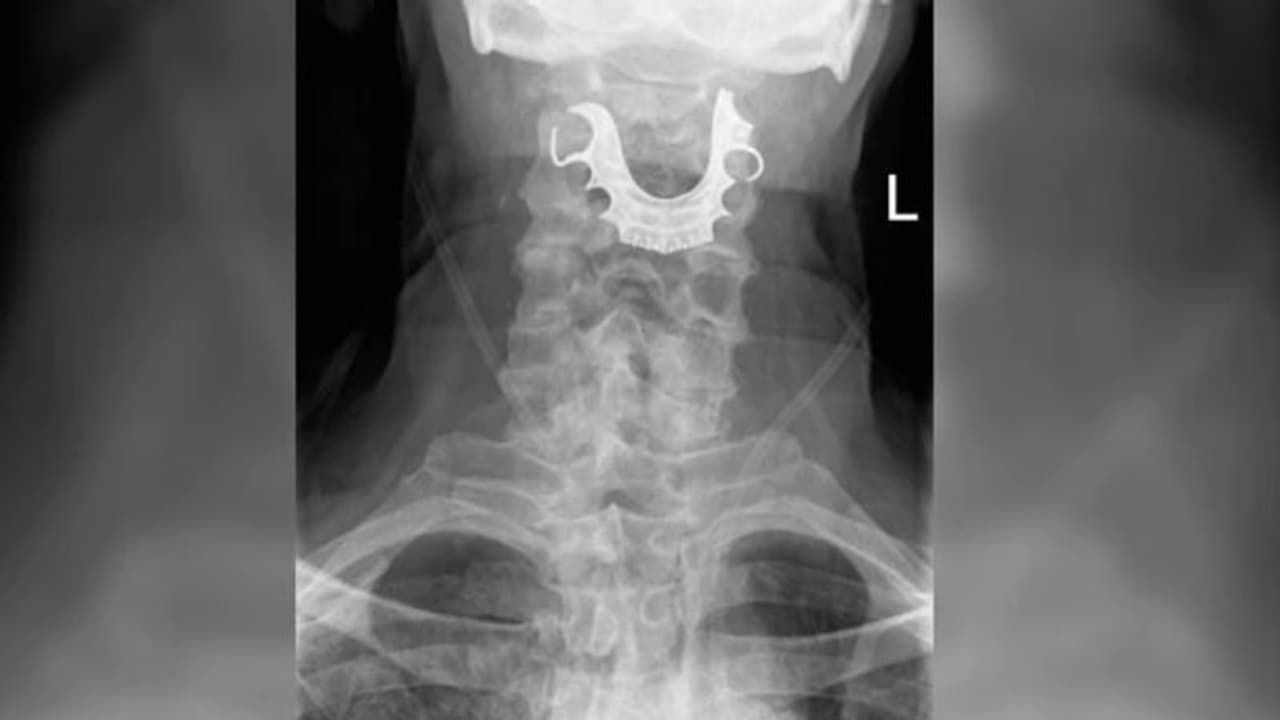

എന്റോസ്കോപ്പി എടുത്തപ്പോഴാണ് തൊണ്ടയ്ക്കുള്ളില് കുടുങ്ങിയ വെപ്പുപല്ല് ഡോക്ടറുടെ ശ്രദ്ധയില്പ്പെട്ടത്. പിന്നീട് മറ്റൊരു ശസ്ത്രക്രിയകൂടി നടത്തിയാണ് വെപ്പുപല്ല് തൊണ്ടയില് നിന്ന് പുറത്തെടുത്തത്. എന്നാല് ഇതോടെയും ഈ വൃദ്ധന്റെ ആശുപത്രിവാസം അവസാനിച്ചിരുന്നില്ല.